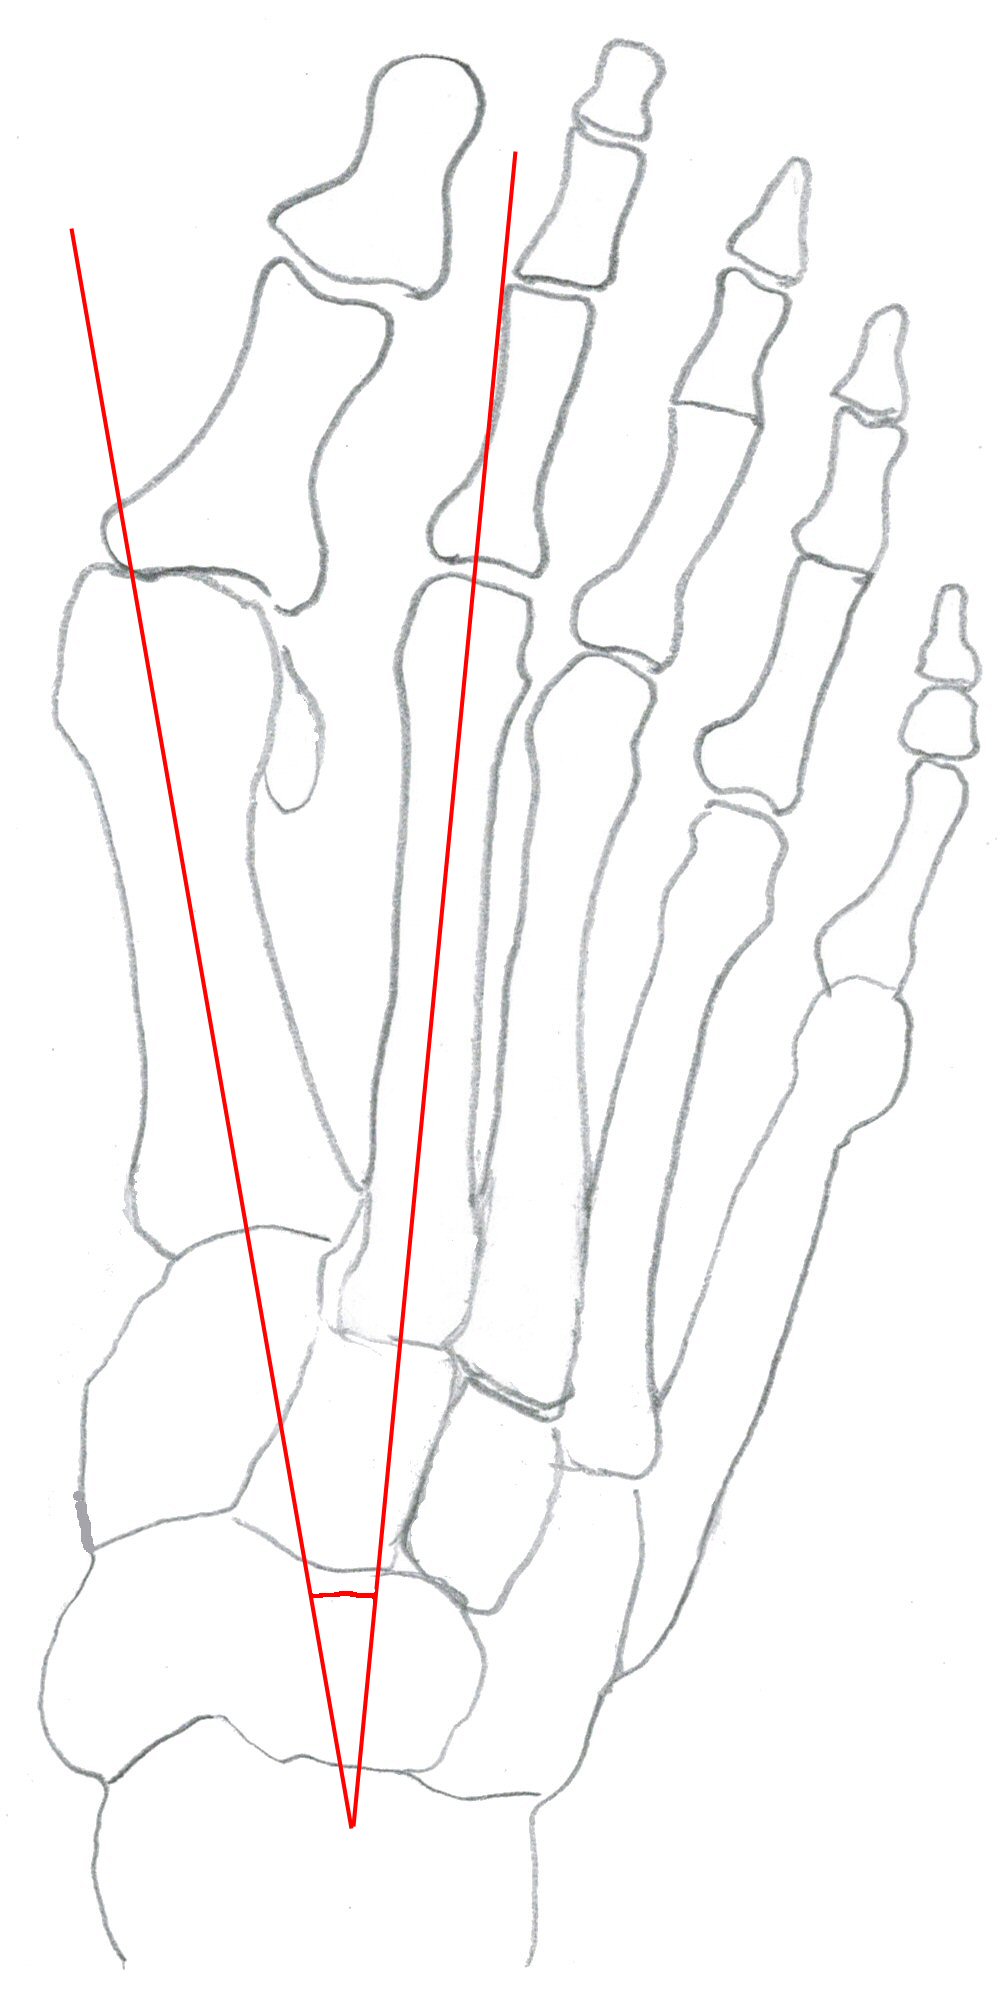

Intermetatarsalvinkel (IM-vinkel): vinkel mellan metatarsale 1 och 2, normalt 10-12°.

Fot med hallux valgus, markerad intermetatarsalvinkel